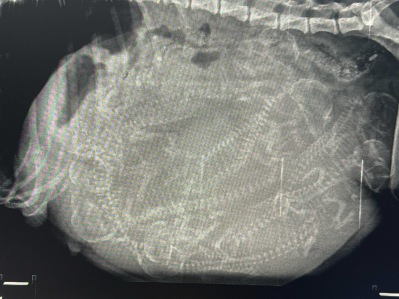

03.06.2025 røntgen

I dag har vi tatt turen til veterinær Eli for å ta røntgen av Anna. Dess større tispene er, jo vanskeligere er det å få et nøyaktig antall valper. Det vi så på bildene var at det garantert er 7 valper, men etter å ha studert bildene nøye mener vi at det er en ekstra valp. Så vil fremtiden vise om det er 7 eller 8 valper